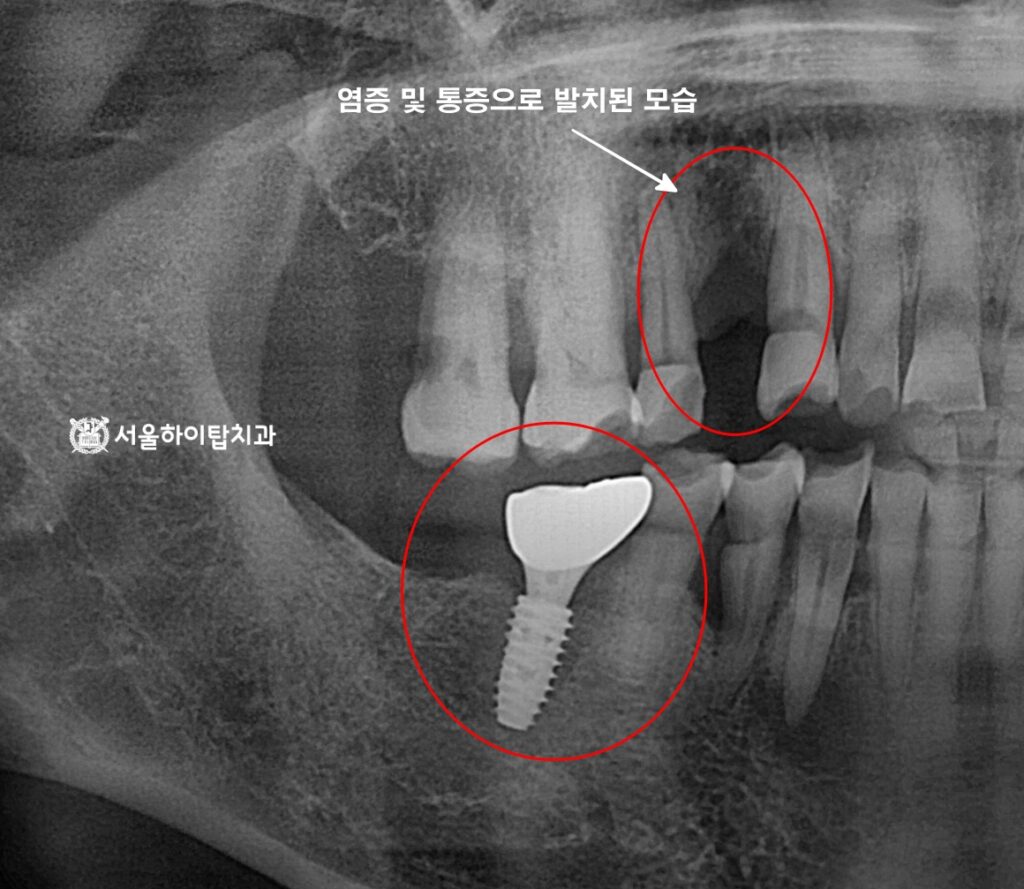

최종 결과

최종 완료된 모습을 살펴보면,

기존 염증이 발생한 치아는 발치가 이루어졌으며,

임플란트 또한 안정적으로 유지되고 있는 모습을 확인할 수 있습니다.

앞으로는 꾸준한 구강 관리와 정기 검진을 통해

임플란트 주위염 등의 합병증을 예방하는 것이 중요합니다.

일반적으로 3~6개월마다 한 번씩 검진을 받고,

올바른 저작 습관과 치주 건강을 유지함으로써,

임플란트의 장기적 안정성과 교합 기능을 지속적으로 확보할 수 있습니다.

무엇보다, 훼손된 주변 자연치들을 하루 빨리 치료하여,

임플란트와 자연치가 균형을 이루는 안정적인 교합 환경을

조성하는 것이 중요합니다.

이를 통해 특정 치아나 임플란트에

과도한 힘이 집중되는 것을 방지하고,

전체 저작 기능을 회복하며, 장기적으로 구강 건강과

심미성을 동시에 확보할 수 있습니다.